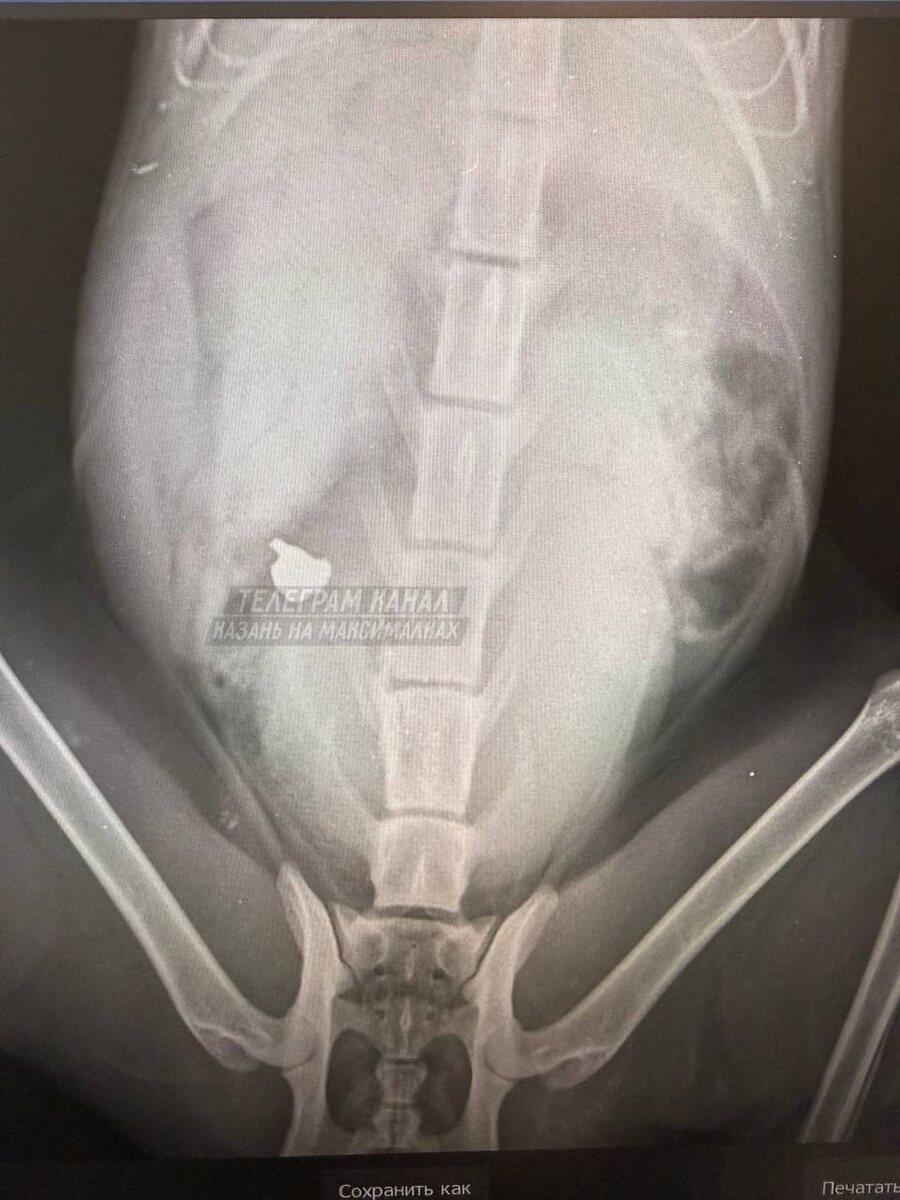

Пишут, что он уже покалечил четырех домашних котов. Один из питомцев получил серьезные травмы, у него поврежден позвоночник, отказали задние лапы. По словам местных жителей, в селе отсутствует участковый, а обращения в администрацию пока не дали результата. Люди требуют установить личность злоумышленника и привлечь его к ответственности. И как рука поднялась? #Кощаково #Татарстан ✅ «В Стране» в MAX

Неизвестный стреляет по котам в селе Кощаково под Казанью. Пишут, что он уже покалечил четырех домашних котов. Один из питомцев получил серьезные травмы, у него поврежден позвоночник, отказали задние лапы.